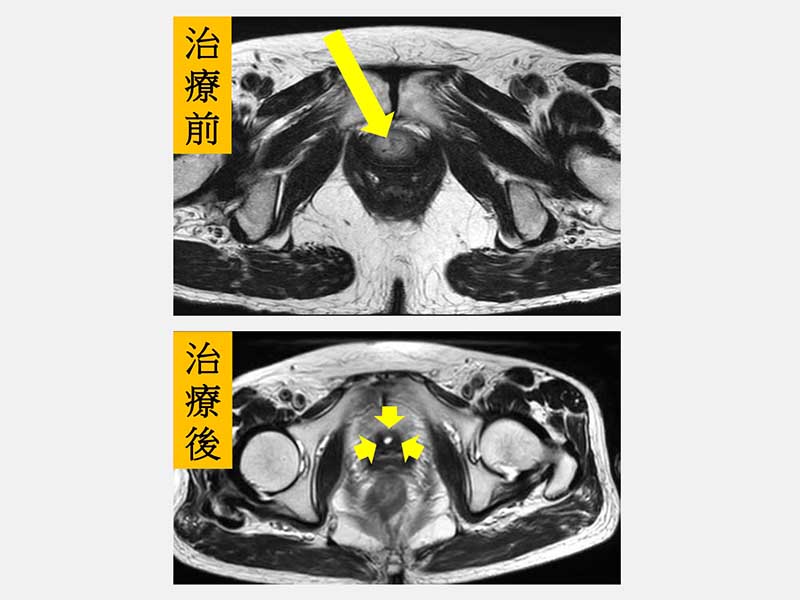

劉緯陽主任指出,李婦一開始很像是典型夏季泌尿道感染的症狀,會有解尿疼痛及血尿,但是以抗生素治療2週後,上述症狀並無明顯改善,而且在尿道口一直有摸到「硬塊」。後來接受進一步尿道鏡檢查,發現其尿道已全部被腫瘤塞滿,深度核磁共振掃描則呈現全段尿道腫瘤已侵犯到陰道壁。

盧皓維主任表示,李婦腫瘤侵犯範圍廣泛,若直接進行手術切除,恐將影響正常泌尿道功能。經劉緯陽主任評估後轉介至放射腫瘤科,並會同血液腫瘤科共同規劃治療策略,爭取泌尿道器官保存的可能性。經跨科團隊充分討論後,最終決定採取根治性同步化學放射治療,以尿道腫瘤作為主要照射目標。由於病灶位置鄰近外陰部的敏感皮膚區域,李婦在治療期間一度出現中度以上的放射線皮膚炎及泌尿道發炎等副作用。然而,在醫療團隊細心照護,以及李婦耐心配合與高度信任下,仍順利完成完整療程。治療結束後,相關副作用皆已恢復,後續追蹤檢查亦顯示腫瘤已消失,治療成效良好。